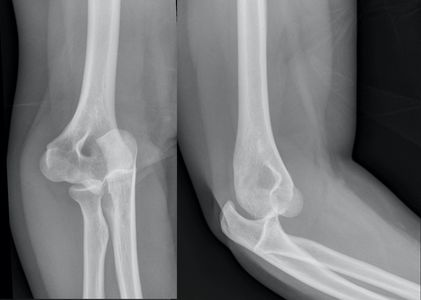

Case example - 20 year old female fell 2m onto crash mat in gym. Elbow in flexion, hand/wrist impact on mat.

XR image shows lateral, AP and oblique views.